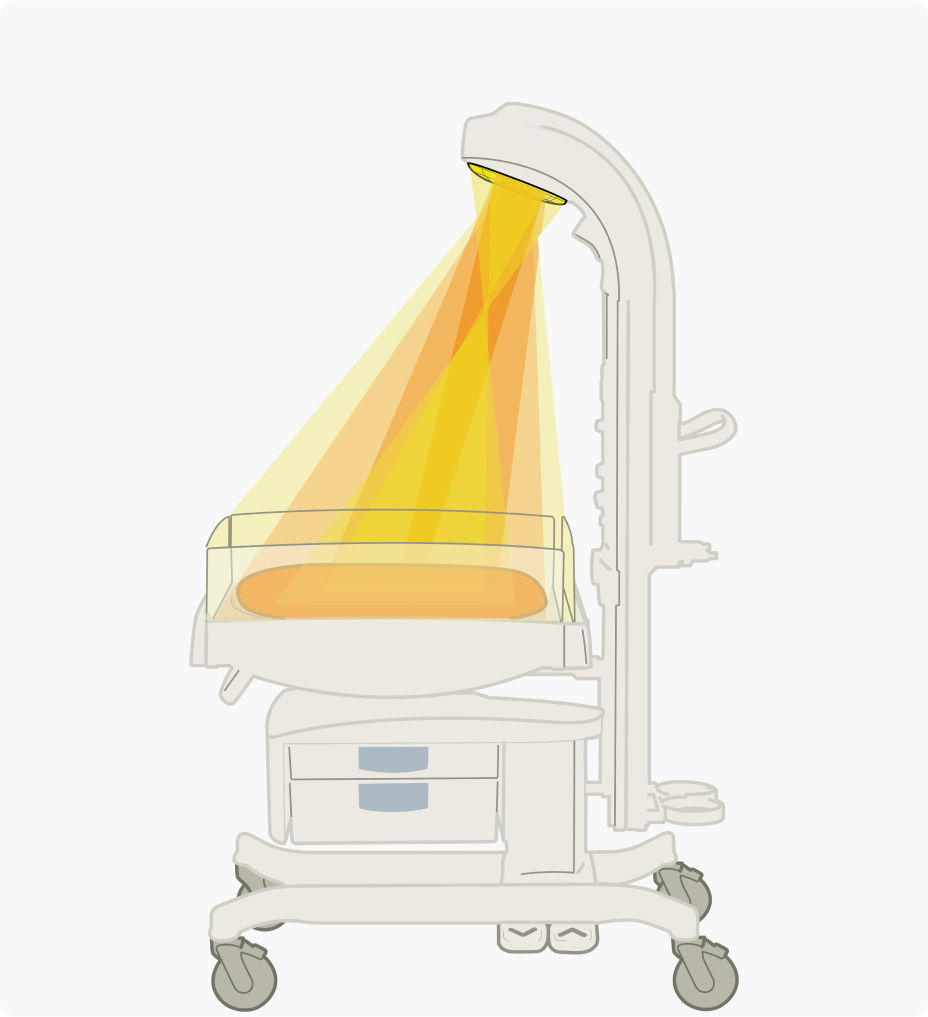

An innovative heater design lets you access your patients